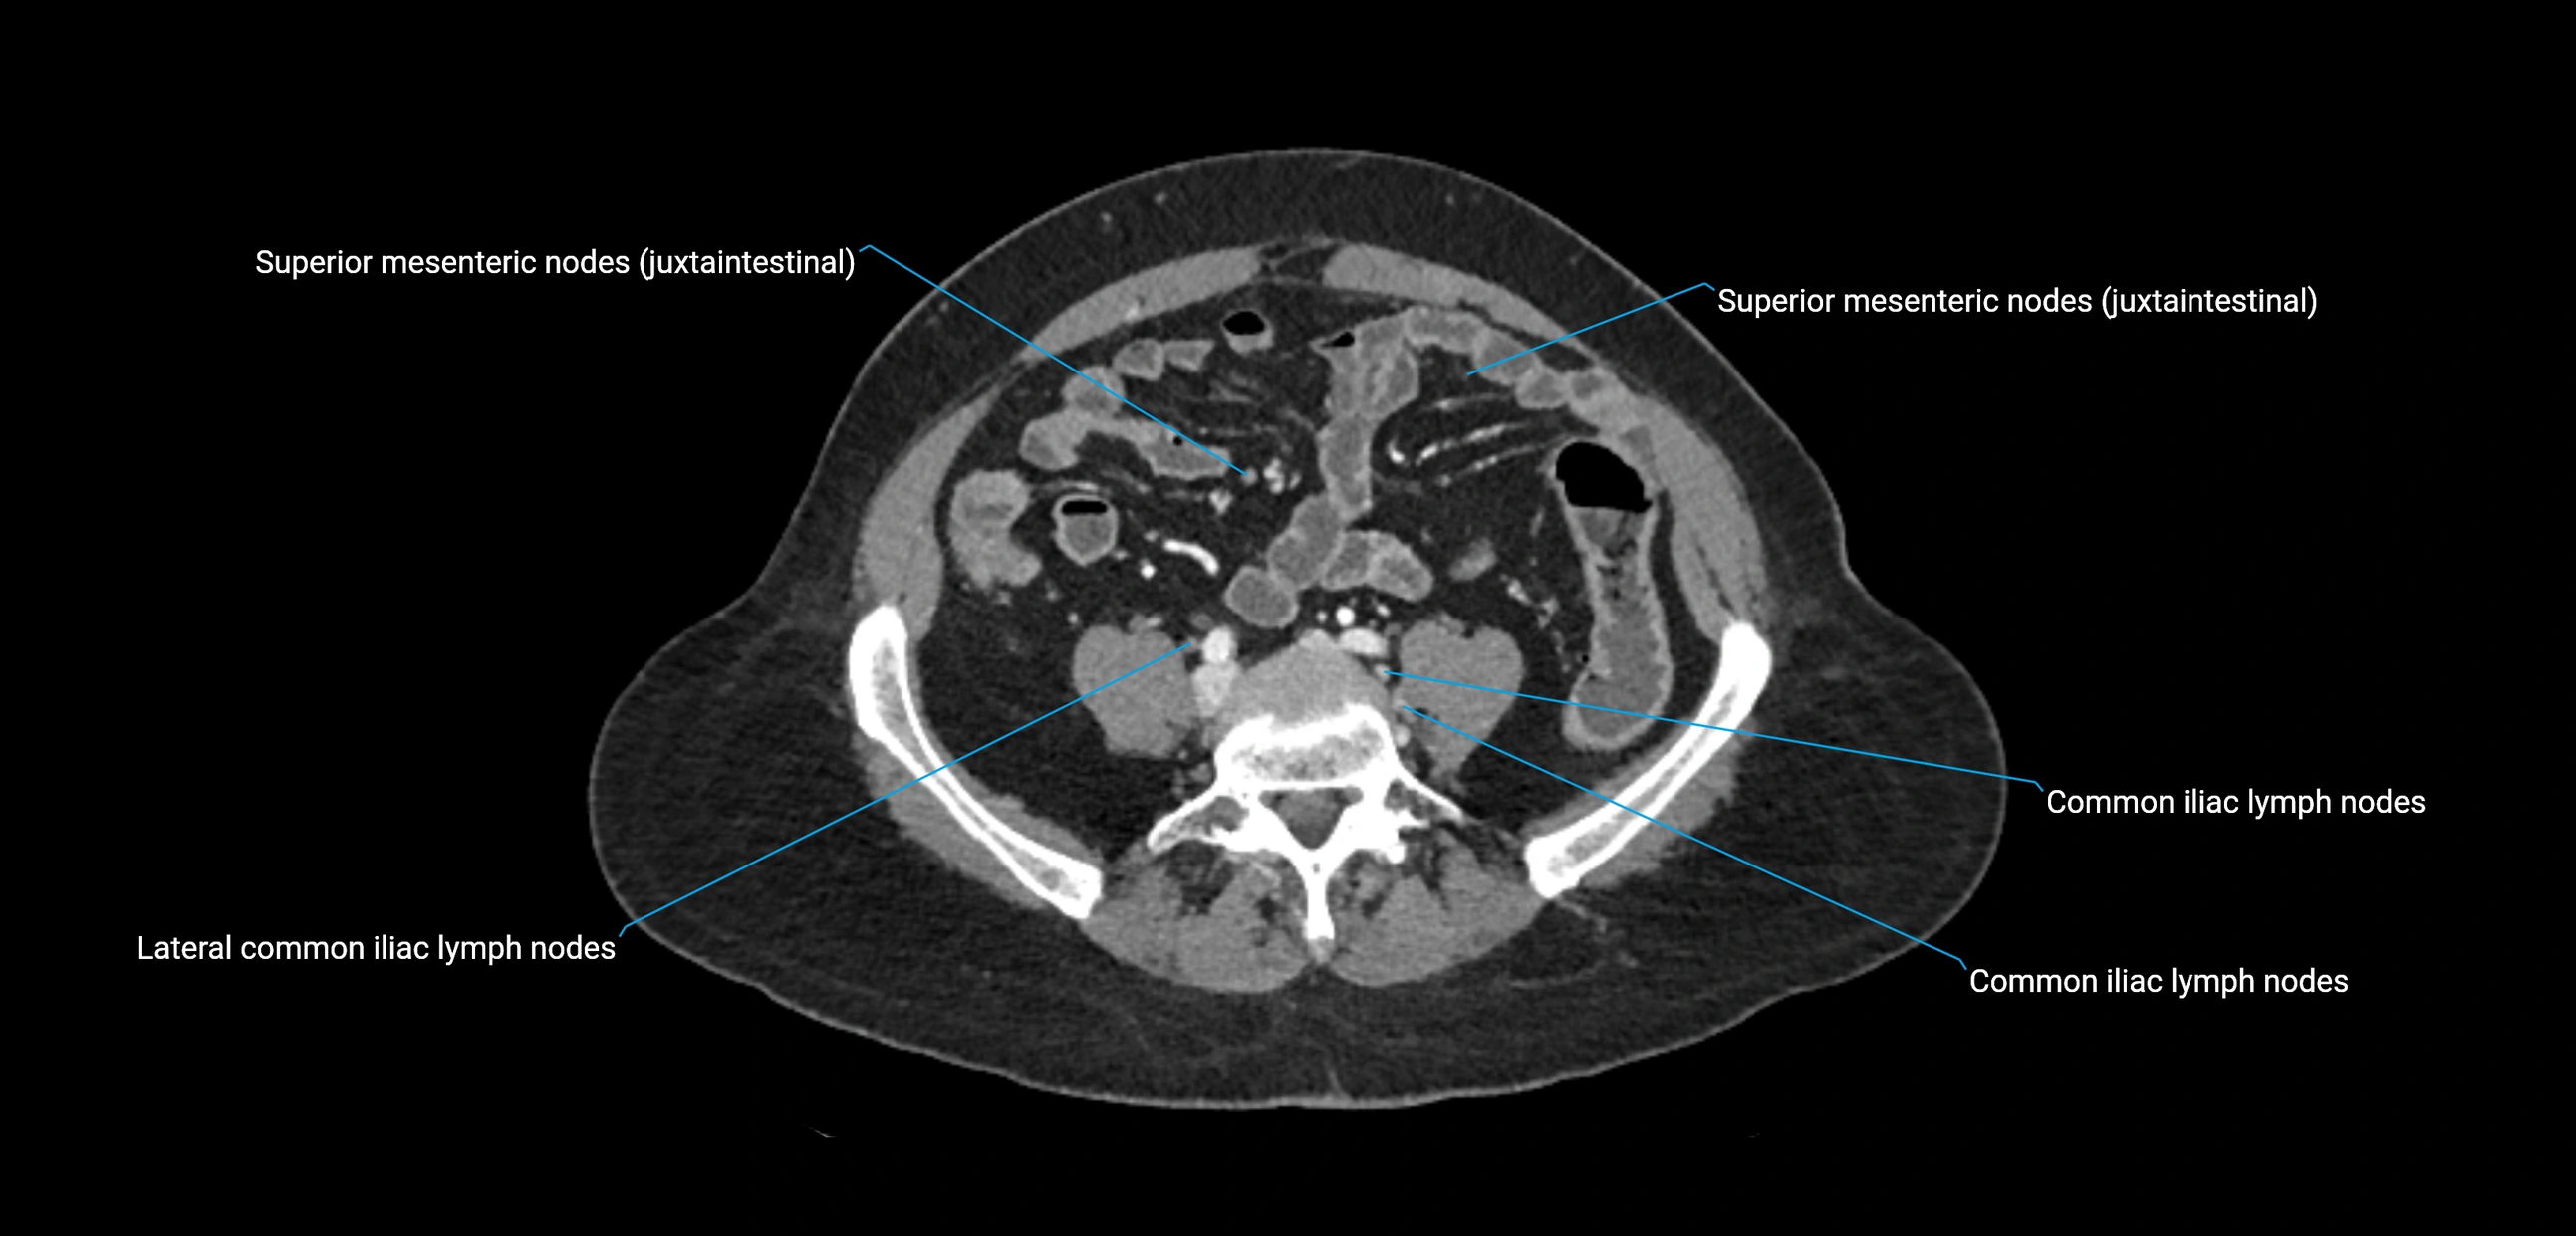

CT Appearance

CT Post-Contrast:

• Normal nodes enhance homogeneously

• Malignant nodes may show heterogeneous enhancement, central necrosis, or conglomerate formation

• Size >1 cm short axis is suspicious, though morphology and distribution are equally important

CT Venography (CTV):

• Demonstrates nodal encasement or compression of adjacent vessels (aorta, IVC, renal veins)

• Useful in staging testicular and ovarian malignancies

• Provides 3D reconstructions for retroperitoneal lymph node dissection planning